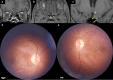

Tuberculosis (TB) is a global health concern and central nervous system (CNS) TB leads to high mortality and morbidity. CNS TB can manifest as tubercular meningitis, tuberculoma, myelitis, and arachnoiditis. Neuro-ophthalmological involvement by TB can lead to permanent blindness, ocular nerve palsies and gaze restriction. Visual impairment is a dreaded complication of tubercular meningitis (TBM), which can result from visual pathway involvement at different levels with varying pathogenesis. Efferent pathway involvement includes cranial nerve palsies and disorders of gaze. The purpose of this review is to outline the various neuro-ophthalmological manifestations of TB along with a description of their unique pathogenesis and management. Optochiasmatic arachnoiditis and tuberculomas are the most common causes of vision loss followed by chronic papilloedema. Abducens nerve palsy is the most commonly seen ocular nerve palsy in TBM. Gaze palsies with deficits in saccades and pursuits can occur due to brainstem tuberculomas. Corticosteroids are the cornerstone in the management of paradoxical reactions, but other immunomodulators such as thalidomide and infliximab are being explored. Toxic optic neuropathy caused by ethambutol necessitates careful monitoring and immediate drug discontinuation. Cerebrospinal fluid diversion through ventriculo-peritoneal shunting may be required in patients with hydrocephalus in stage I and II of TBM to prevent visual impairment. Early diagnosis and prompt management are crucial to prevent permanent disability. Prevention strategies, public health initiatives, regular follow-up and timely intervention are essential in reducing the burden of CNS TB and its neuro-ophthalmological complications.